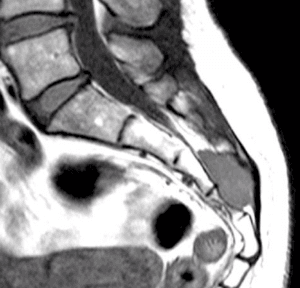

Meningioma dorsal intra raquideo

Masculino, 72.

Lumbalgia de un año de evolución, constante, no mecánica, con mala respuesta al tratamiento médico.